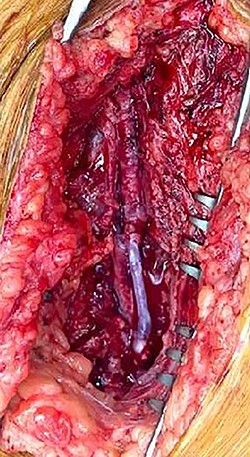

During operative intervention, a hematoma was observed involving muscle tissues in the anteromedial region of the thigh. There were no obvious signs of active infection. The proximal control obtained, the aneurysm incised and the distal control obtained. The aneurysm resected and samples collected for anatomopathological and microbiological analyses (Fig. 4). Reconstruction was performed by interposition of the ipsilateral great saphenous vein in reverse, with end-to-end anastomosis taking into consideration the diameter of the femoral artery (Fig. 5). Intraoperative tissue cultures were negative and the anatomopathological analysis showed a histopathological aspect corresponding to a PSA of the femoral artery, with the absence of the arterial wall and without specific character.

The patient was operated as an emergency. A voluminous hematoma was observed involving muscle tissues in the anteromedial region of the thigh. Proximal control was obtained, the aneurysm incised and the distal control obtained with a fogarty catheter. The hematoma was evacuated and the PSA was resected. The anatomical structures are hardly recognizable and deformed due to the presence of this important hematoma. Our old venous bypass was not visualized, probably compressed and evacuated with the hematoma. The reconstruction performed by interposition of graft (Dacron 6 mm), with end-to-side anastomosis.